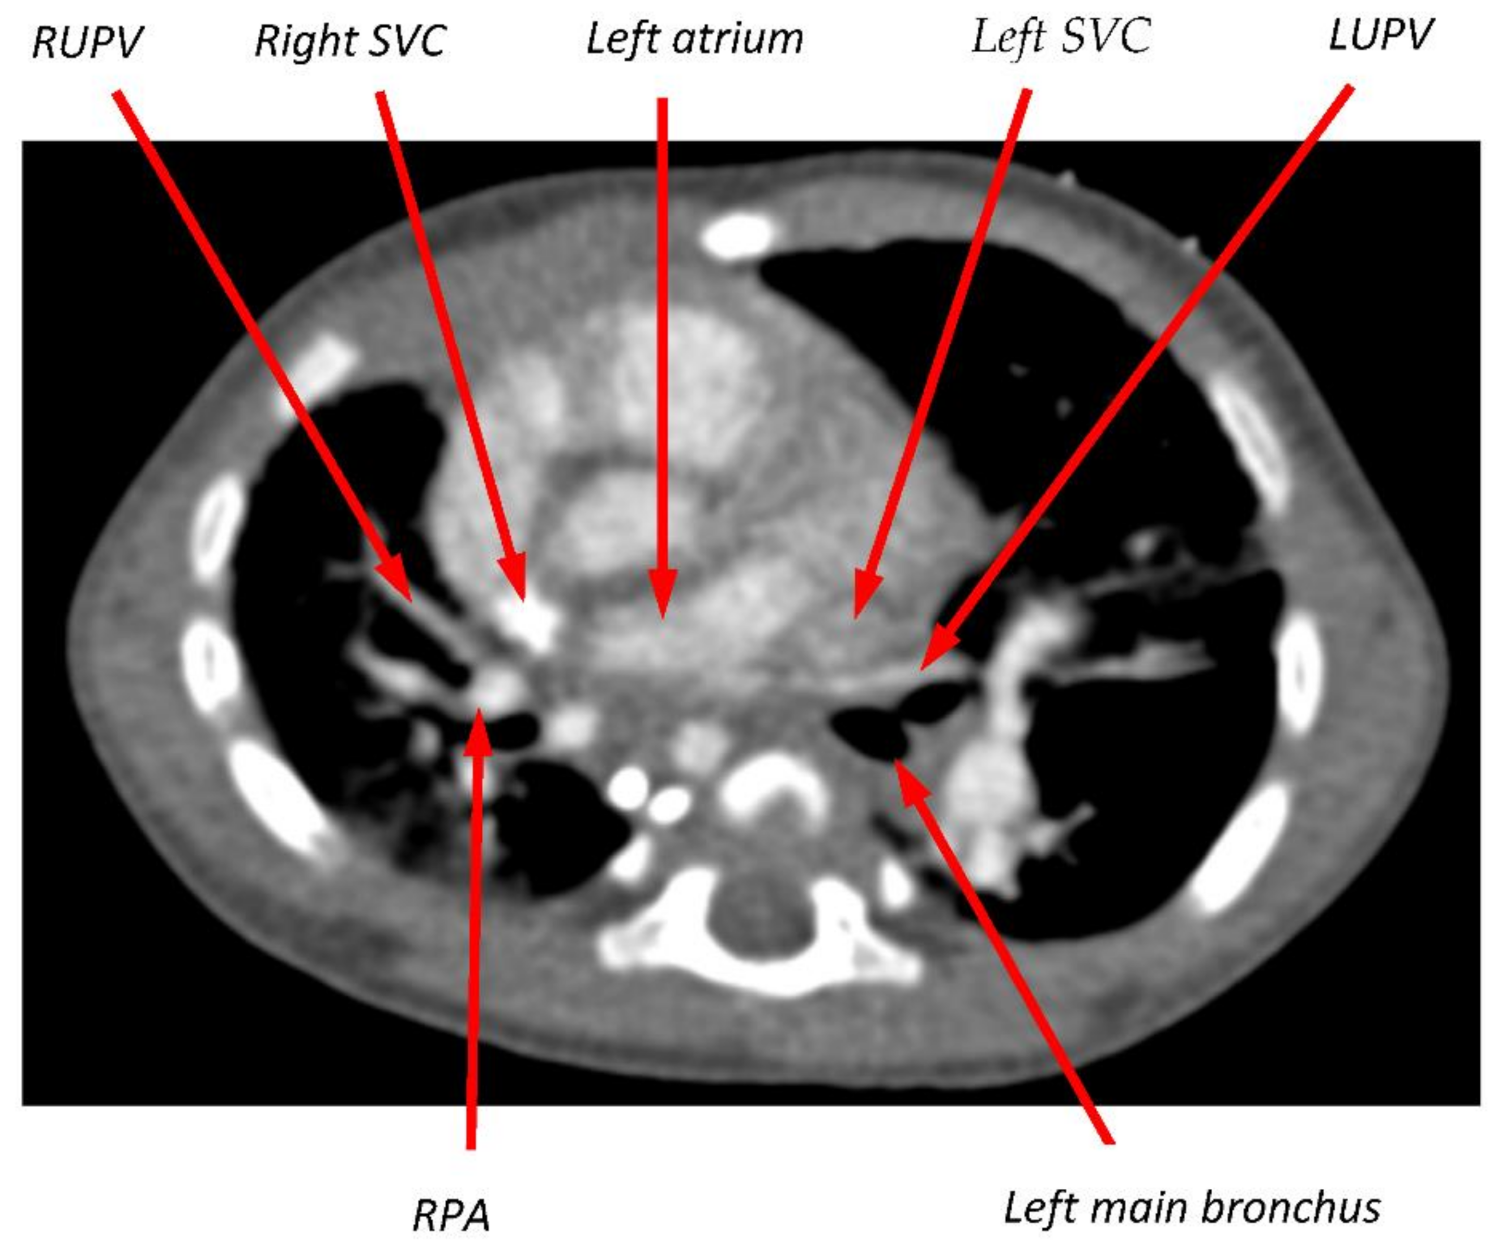

2.2. Case 1

2.3. Case 2